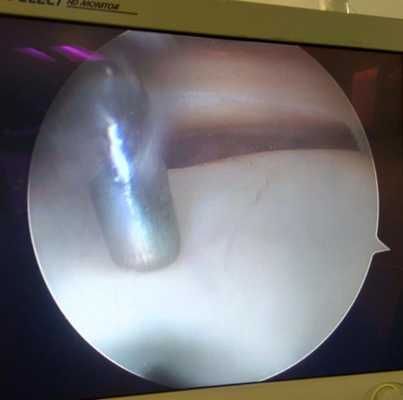

В проекции суставной щели (коленного, плечевого, голеностопного, локтевого, других суставов) делают два-три маленьких разреза-прокола (порта). В один из них вводят тонкий оптический прибор - артроскоп, диаметром 2-4 мм, длиной 12-14 см, который соединен с цифровой видеокамерой. Через другой порт вводят специальный щуп или тонкие инструменты.

Ход операции хирург контролирует, глядя в монитор, где имеется увеличение изображения в 30 - 50 раз по сравнению с реальными размерами всех внутрисуставных структур. Такая методика обеспечивает высочайшую точность манипуляций в суставе и исключительную аккуратность манипуляций.

Изображение полости сустава.

В целях высокоинформативной диагностики специалист через микропортал вводит рабочую трубку устройства внутрь сустава, в которую вмонтированы система ультрасильных линз, мощный световой источник и видеозаписывающая цифровая техника. Все структуры, что «видит» артроскоп, визуализируются на экране в «живом» виде, причем изображение поступает в многократно увеличенном формате. Врач может найти точное расположение травмы или дегенеративных изменений, установить характер патологии, степень тяжести и принять меры.